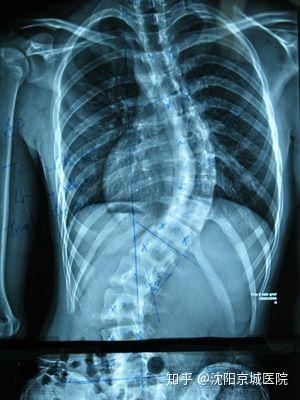

強直性脊柱炎的癥狀

強直性脊柱炎的主要癥狀包括下腰部疼痛、僵硬和關節活動受限,患者可能在早晨或長時間坐立后感到明顯的不適,隨著病情的進展,癥狀可能逐漸加重,影響胸椎和頸椎,導致呼吸困難、駝背等,部分患者還可能出現疲勞、發熱、食欲不振等全身癥狀。